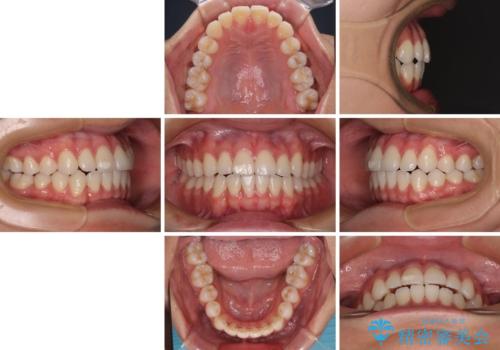

- 前歯のデコボコと奥歯の咬み合わせを気にして来院された患者様です。

右側の奥歯は、上が外側に転位した鋏状咬合を呈しており、前歯のデコボコ改善と並行して咬み合わせを改善していく必要がありました。

ワイヤー装置でもマウスピースでも、どちらでも適用の症例でしたが、片側の鋏状咬合はマウスピース矯正ではしっかりと改善できる可能性が低いことや、何と言っても自己管理の煩わしさがないことから、ワイヤー装置を選択されました。